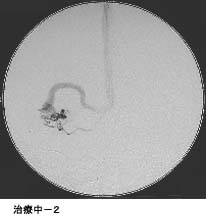

(2)脳動静脈奇形に対する液体塞栓物質を用いた治療

*治療により異常血管は閉塞されました。